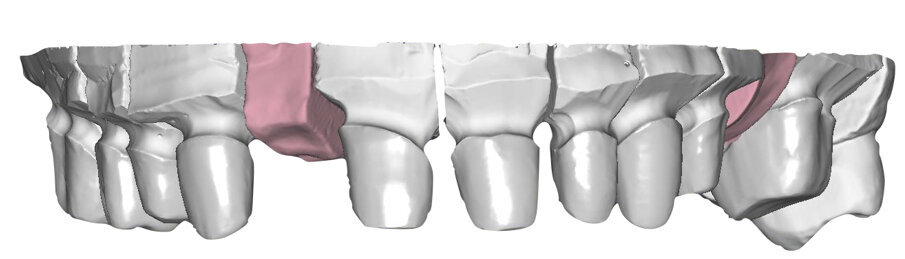

Si esegue perciò cefalometria (Fig. 8) su radiografia latero-laterale (Fig. 9) e axiografia dei movimenti limite (Cadiax Compact, Gamma Dental) (Fig. 10) per la programmazione di un articolatore a valori medi (Artex TR, AmmanGirrbach) e montaggio dei modelli con arco faciale, che confortano nella produzione di un primo provvisorio prelimatura con rialzo arbitrario della VDO di 5 mm sull’asta incisale e miglioramento di OB e OJ, a scopo pre-terapeutico interlocutorio e di immediata risoluzione estetica. Conclusa la necessaria terapia causale e restaurativa viene eseguita la scansione intraorale delle arcate (TRIOS 3 Pod, 3Shape) (Figg. 11-14) e del rapporto articolare con cera di RP (Fig. 15). La scansione è stampata (VisiJet RWT, 3D Systems) con monconi sfilabili tramite stampante 3D (ProJet MJP 2500 Plus, Selltek) (Figg. 16-20), i modelli derivanti sono zoccolati e montati con cere di RP e arco faciale su articolatore a valori individuali (Reference SL, Gamma Dental). La programmazione dell’articolatore derivante dalla registrazione axiografica è ora eseguita come da indicazioni del software (Gamma Dental software, sia per l’uso degli inserti condilari ed incisali, sia per la definizione degli angoli di SCI e di Bennet (Fig. 21). Lo spazio protesico risultante a una VDO adeguata alla riabilitazione dei denti anteriori vitali, con anatomia non ulteriormente modificabile, è insufficiente per uno stabile ripristino dei rapporti occlusali, specie nei tragitti funzionali. Si decide perciò di impiegare due inserti rossi di programmazione di protrusiva (+2 mm) per riposizionare la mandibola in TRP (Figg. 22, 23).

Ciò consente un miglioramento dei rapporti interarcata, un guadagno di spazio protesico in regioni premolari e molari, ed il mantenimento di uno spazio protesico conforme ad una corretta anatomia per i denti vitali da 1.3 a 2.3. Al paziente viene pertanto aggiornato il piano di trattamento e proposta la riabilitazione in TRP, con la previsione di overlays all’arcata inferiore per costruzione del nuovo piano occlusale. In posizione terapeutica sono modellati i coni delle centriche attive sui monconi sfilabili all’arcata inferiore, per la successiva individuazione al CAD con modulo articolatore del piano occlusale studiato. Questo rapporto articolare in TRP è ora scansito con scanner da laboratorio Xanos Evo Scan Compact (Fig. 24).

I modelli sono così importati in corretta posizione spaziale tramite il modulo exocad Virtual Articulator (Fig. 25). Non avendo a disposizione nel CAD l’analogo virtuale dell’articolatore Reference SL, viene impostato il sistema virtuale SAM, che usa lo stesso piano di riferimento axio-orbitale e geometria sovrapponibile al Reference SL. Per la programmazione virtuale dei parametri funzionali dell’articolatore si riesegue l’output dall’axiografia elettronica con Gamma Dental per SAM (Fig. 26). Si procede perciò ora con la modellazione CAD della ceratura mantenendo il riferimento dato dal piano occlusale individuato dai coni di centrica scansiti con l’articolatore (Fig. 27). L’articolatore virtuale consente una prima verifica dei rapporti occlusali tra gli elementi e un abbozzo di funzionalizzazione delle cuspidi con strumenti virtuali dinamici, che permette di arrivare ad un CAD design vicino alla morfologia ricercata (Figg. 28-33). Il modellato è ora fresato in cera Yeti Dental al CAM con fresatore VHF Cam5-S1 ed i denti in cera, tutti singolarmente sfilabili, sono posizionati sui modelli eseguiti con stampa 3D.